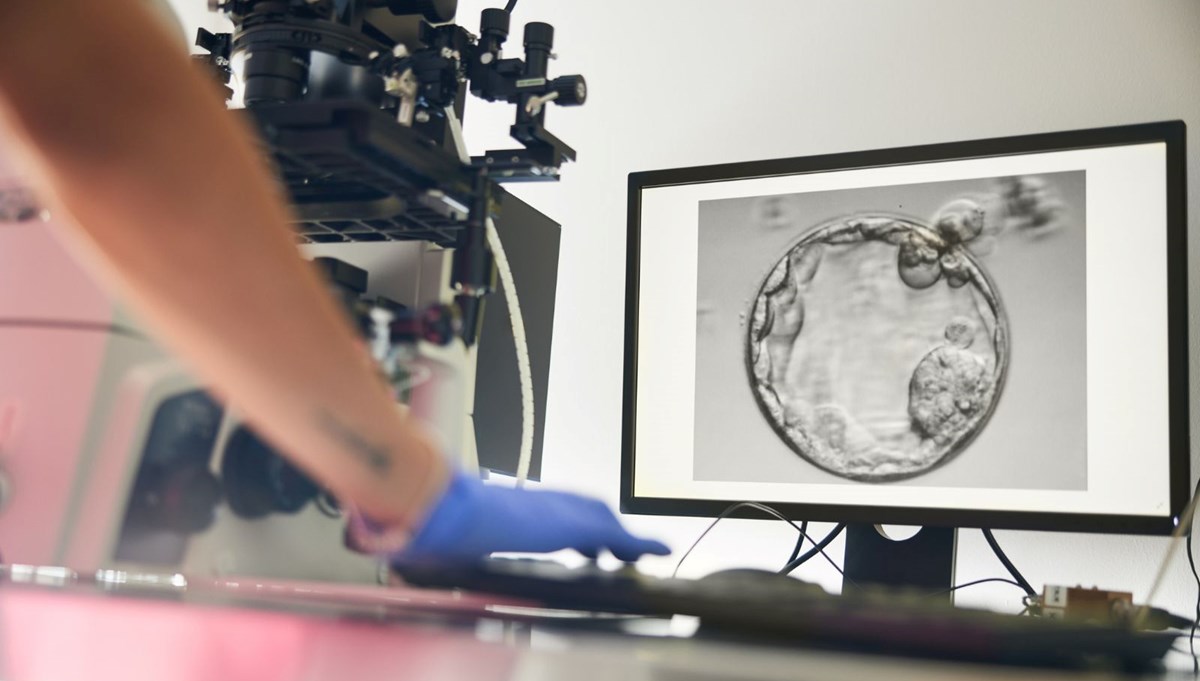

Nature Communications dergisinde yayımlanan araştırmada, bilim insanları sıradan bir insan deri hücresinin çekirdeğini (genetik bilginin büyük bölümünü taşıyan yapı) alıp, çekirdeği çıkarılmış bir donör yumurtaya aktardı.

Bu yöntemle 82 işlevsel insan olgunlaşmamış yumurta hücresi üretildi ve laboratuvar ortamında döllenme sağlandı.

Araştırma ekibi, doğal hücre bölünmesini taklit ederek fazla kromozomları ayıklayan ve geride 23 kromozom bırakan bir yöntem geliştirdi. Bu sürece “mitomeyoz” adı verildi. Ancak üretilen yumurtaların yalnızca yüzde 9’undan daha azı, döllenme sonrası embriyo gelişiminin kritik aşaması olan blastosist evresine (5–6 günlük gelişim) ulaşabildi. Üstelik ortaya çıkan tüm embriyolar kromozom bozuklukları taşıyordu.